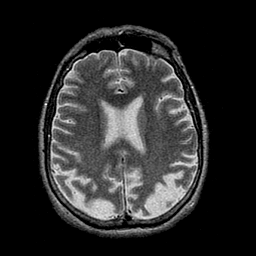

Alzheimer's disease: overlay -- Slice #33

[Home][Help][Clinical] Slice 33